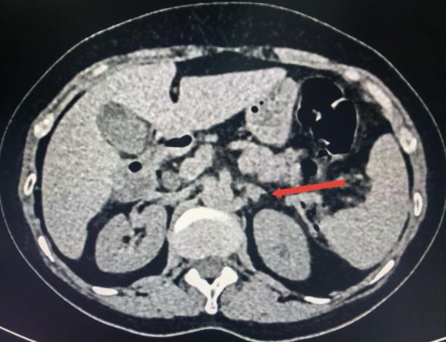

近日,新城院区泌尿外科收治了一名被阵发性头痛、头晕困扰2月余的女性患者,患者同时伴有恶心、大汗等症状,严重影响日常生活。入院后,监测血压最高达170/110mmHg,肾上腺CT检查提示其左侧肾上腺存在4mm占位病变,然而肾上腺相关内分泌化验未显示典型异常,血钾水平也处于正常范围,病情诊断面临一定挑战。